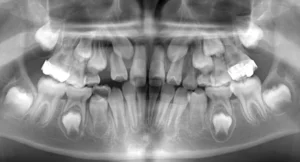

【大人の矯正】叢生・埋伏歯・下の歯が1本飛び出している・非抜歯症例・32歳女性【E.M様】

初診時年齢(性別) 30~39歳 (女性) 費用の目安 1017560円

【大人の矯正】叢生・埋伏歯・出っ歯・乳歯がなかなか抜けない12歳女児【R.T様】

初診時年齢(性別) 小学校6年生 (女性) 費用の目安 650000円

【大人の矯正】叢生・埋伏歯・歯が骨の中でゆがんでいる・13歳女性【A.H様】

初診時年齢(性別) 小学校1年生 (女性) 費用の目安 610000円

【子供の矯正(一期)】叢生・埋伏歯・受け口・永久歯が生える隙間がない・非抜歯症例・9歳女子【K.T様】

初診時年齢(性別) 小学校2年生 (女性) 費用の目安 501270円

【子供の矯正(一期)】埋伏歯・すきっ歯・7歳男子 【T.N様】

初診時年齢(性別) 小学校1年生 (男性) 費用の目安 350000円